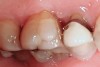

Figure 5  The red, irregular surface on the palatal surface of a maxillary molar can be an early sign of reflux.

Figure 5

Figure 6  Continued damage from erosion produced by GERD. Other areas of erosive damage will be dictated by the sleep posture of the patient.

Figure 6